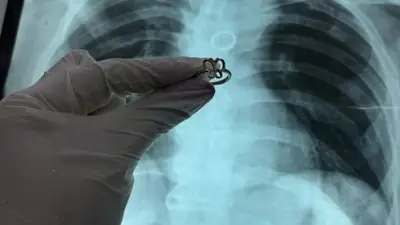

En un hecho que sorprendió a la comunidad médica del Cono Sur, especialistas del Instituto Nacional de Enfermedades Respiratorias y del Ambiente (Ineram) de Paraguay lograron extraer con éxito un anillo de oro del pulmón de un paciente. El hombre, oriundo de la localidad de San Pedro de Ycuamandiyú, había sido trasladado a la capital, Asunción, para un procedimiento de mantenimiento de su cánula de traqueostomía cuando los médicos detectaron una anomalía en sus estudios de imagen.

"Se le realizó una radiografía de tórax y una tomografía donde se observó claramente un objeto metálico incrustado en el bronquio izquierdo", señaló Morínigo en declaraciones a medios locales. La intervención requirió retirar temporalmente la cánula de traqueostomía para proceder a la extracción del cuerpo extraño, confirmando que se trataba de una joya de oro puro.

El Dr. Morínigo destacó que la naturaleza del metal fue determinante para la supervivencia del paciente. "Tuvo muy buena suerte de que fuera oro puro. Si hubiera sido una joya de fantasía o de otro metal, la oxidación y la herrumbre habrían perforado los tejidos pulmonares en poco tiempo, provocando consecuencias fatales", puntualizó el especialista. Tras la exitosa intervención, el hombre se recupera bajo vigilancia médica en el centro especializado.